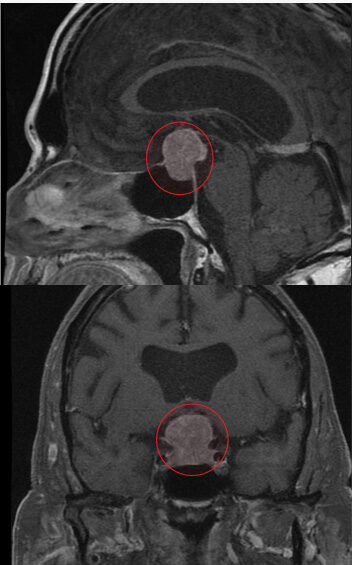

MRI of pituitary macroadenoma circled in red